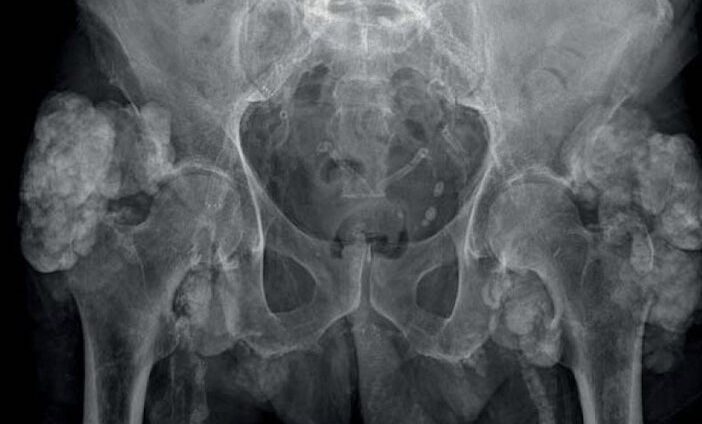

Bài viết trình bày bệnh nguyên, chẩn đoán và xử trí cốt hoá lạc chỗ, một biến chứng thường gây đau, hạn chế chức năng và giảm chất lượng cuộc sống ở nhiều bệnh nhân